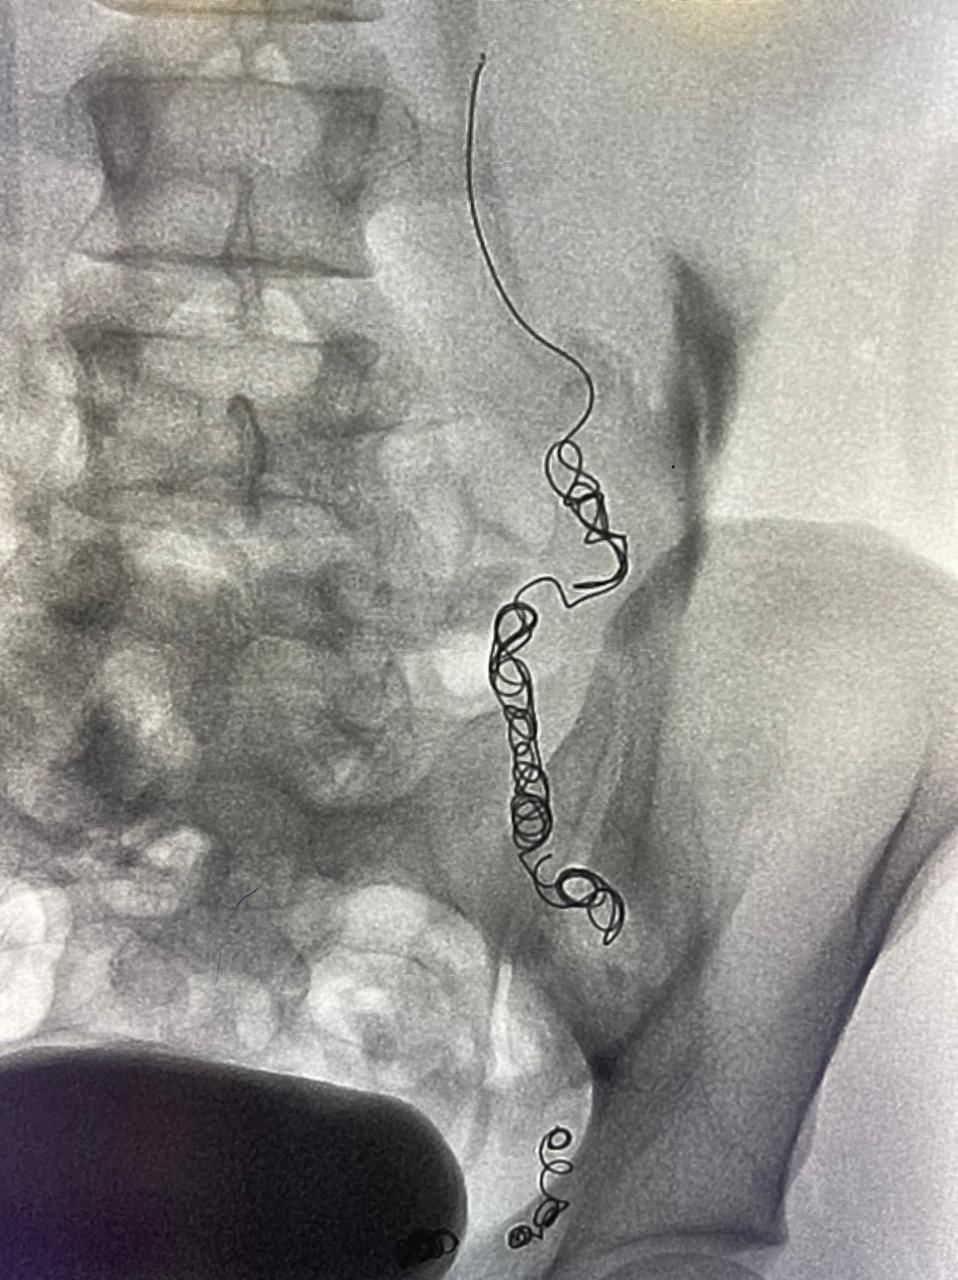

وقد قام الفريق الطبي بقيادة د.محمد شراحيلي استشاري الأشعة التداخلية، باستخدام القسطرة الوريدية حيث تم تحديد واستكشاف جميع الأوردة المسببة لارتجاع الدوالي مرة أخرى، موضحاً علاجها بطريقة اللفائف المعدنية الدقيقة وحقن المادة المتصلبة.

وأضاف:” تساعد تقنيات الأشعة التداخلية باستخدام القسطرة تحت استرشاد الأشعة الصوتية والفلورية من أحدث الطرق العلاجية لدوالي الخصية حيث يتوفر العديد من تقنيات العلاج و منها إغلاق الوريد المتسبب في الدوالي باستخدام اللفائف المعدنية الدقيقة أو من خلال حقن مادة صمغية أو متصلبة، حيث يتم الوصول لتلك الأوردة من خلال فتحة دقيقة بالجلد لذراع المريض لا تتجاوز الـ 2 ملم و لا تترك علامات جراحية على الجلد” .